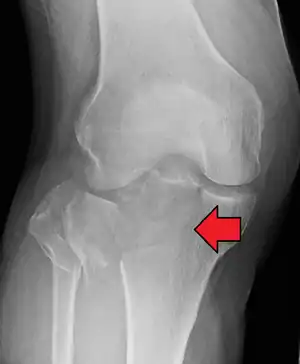

Lateral Tibial Plateau fracture XRay with Depression